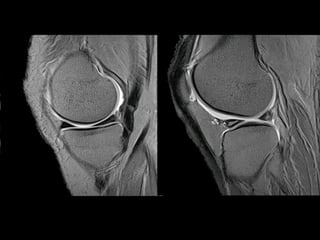

http://www.parksidemri.com/physician/casestudy/case-win03/images/case7.jpg

http://www.parksidemri.com/physician/casestudy/case-win03/fig6.html